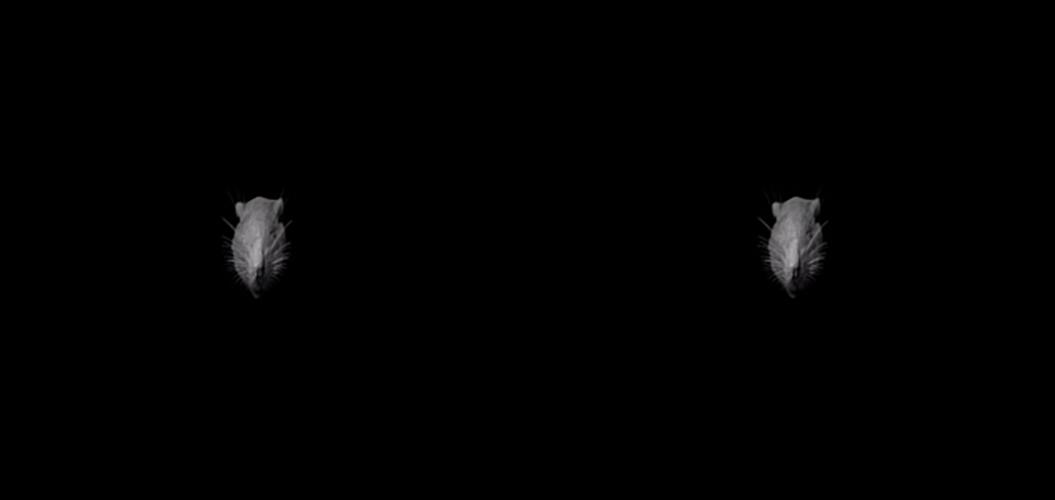

For respiratory research utilising gene vector delivery to the lung, the size of rodent models has typically necessitated relatively “blind” dosing via the nose, via an endotracheal tube, or through a surgical incision into the trachea. This commonly results in a limited ability to reliably dose specific small regions of lung, and contributes to high levels of transduction variability between animals. We have designed and successfully implemented the first reliable targeted gene vector dosing of small regions in rat lungs using a miniature rigid bronchoscope containing a working channel. This method is now published in Human Gene Therapy methods. An example of bronchoscopic dosing into a CF rat lung is shown above.